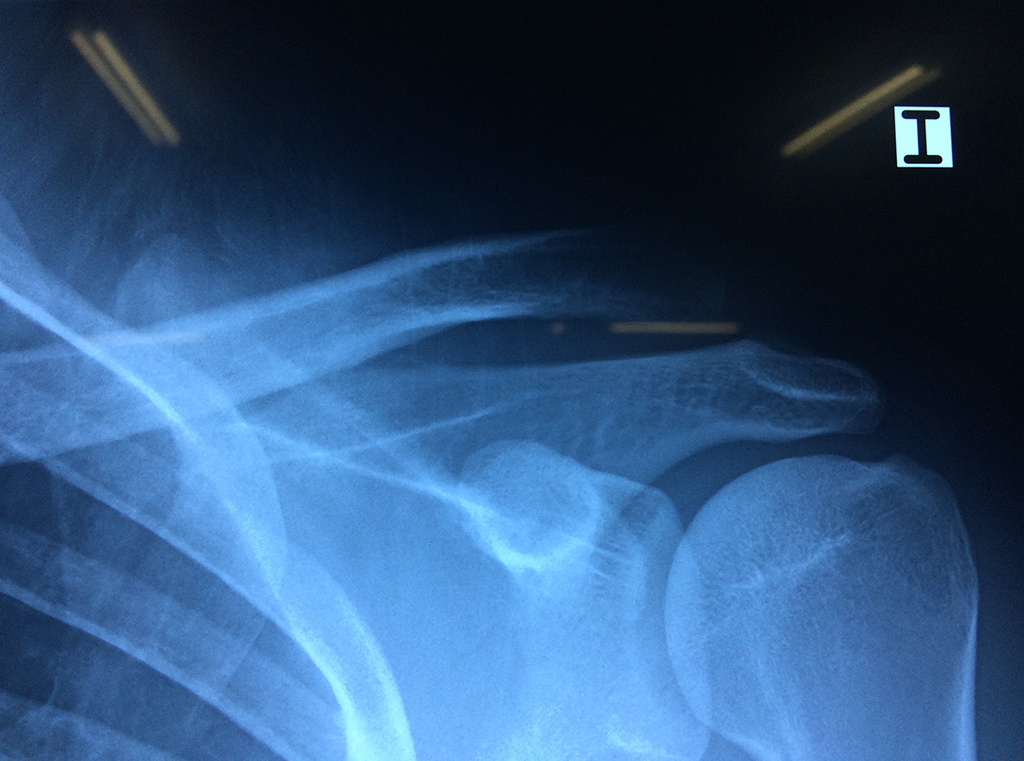

En anatomía humana, el hombro es la parte del cuerpo donde se une el brazo con el tronco. Está formado por la conjunción de los extremos de tres huesos: la clavícula, la escápula y el húmero; así como por músculos, ligamentos y tendones.

Exteriormente una envoltura de tejido blando circunda el conjunto, es la llamada cápsula articular que está reforzada por varios ligamentos que le dan estabilidad e impiden que los huesos se desplacen más allá de sus límites fisiológicos. Un conjunto de músculos y sus tendones se unen a las superficies de los huesos y hacen posible la movilidad de la articulación, entre ellos es muy importante el manguito rotador formado por cuatro músculos que proporcionan movilidad y estabilidad al hombro.